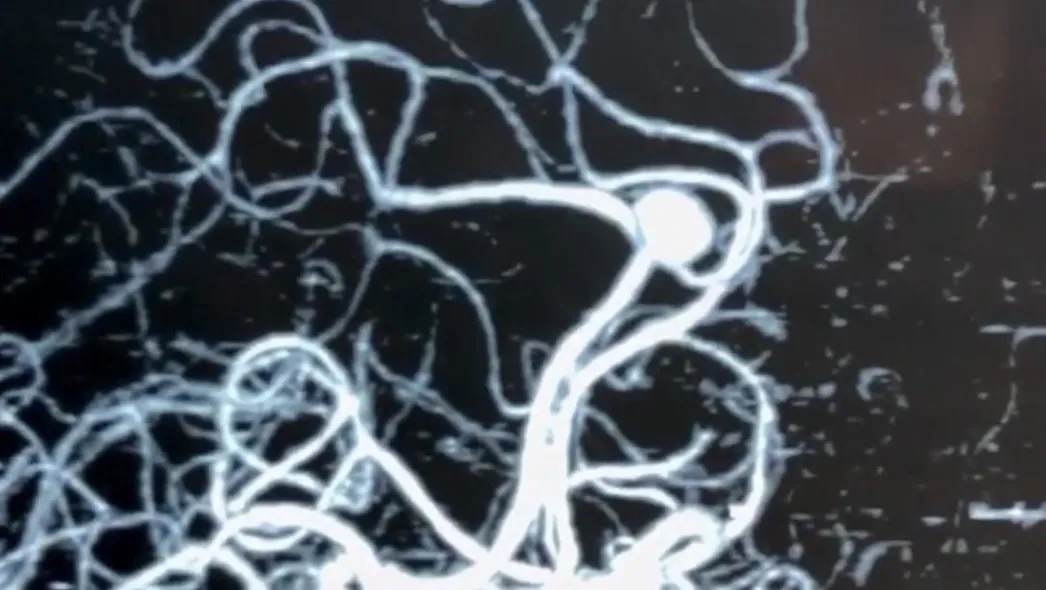

Аневризмы мозговых артерий – это патология сосудов, при которой происходит выпячивание стенки артерии. По форме выпячивания различают мешотчатые и веретенообразные (фузиформные) аневризмы. Причина появления аневризма доподлинно неизвестна. Среди этиологических факторов могут выступать врожденные предрасположенности (дефекты мышечного слоя стенки мозговых сосудов); атеросклеротические (сочетаются с врожденными дефектами стенки мозговых сосудов); Эмболические, инфекционные, травматические факторы

МРТ головного мозга, церебральная ангиография, КТ-ангиография.